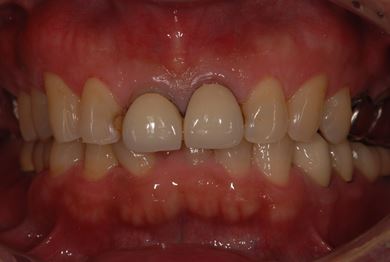

インプラントの症例写真 IMPLANT

インプラント治療

| 性別/年齢 | 男性 / 59歳 | ||||||||||||||||||||||||||||||||

| 主訴 | インプラント治療を検討中。 | ||||||||||||||||||||||||||||||||

| 治療方針 | 欠損部分インプラント治療により、機能的・審美的回復を行う。 | ||||||||||||||||||||||||||||||||

| 治療内容 | インプラント2本、ハイブリッドセラミック2本 | ||||||||||||||||||||||||||||||||

| 総治療費 | 738,675円 | ||||||||||||||||||||||||||||||||

| 治療期間 | 8ヶ月 |